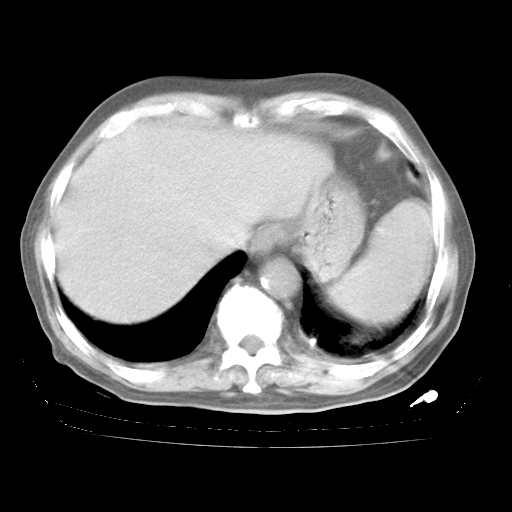

4月28日肺部CT

个人阅读4.14日肺部CT平扫:纵隔窗无异常,但肺窗示:双下肺内、后基底段有片絮状侵润影,部位以后基底段为著,以间质改变为主,呈急性肺泡炎征像,和首次住院影像学有相似之处。仅是个人读片,明日请相关专家再读片哈。其它建议同上。

今请临免主任会诊后认为:4月14日胸部CT已有双下肺间质性改变。患者病情复发多系激素减量过快不正规所致。目前甲强龙80mg/日,一周后酌情开始减量,不易过快。环磷酰胺若已停用,暂不使用。他同意目前抗菌药物使用,但应考虑是否加用B-内酰胺类抗菌药物(中性细胞明显增高);2、结核复发目前依据不足;3、若免疫全套各项指标正常,考虑多系特发性肺间质炎可能大。4、加强支持,并注意保护胃黏膜。